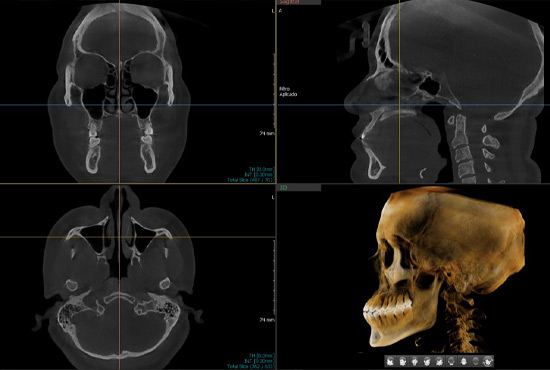

La Tomografía Cone Beam ofrece imágenes 3D detalladas del maxilar y los dientes, permitiendo diagnósticos precisos y una planificación eficaz de tratamientos complejos.

Este software especializado permite analizar y manipular imágenes 3D obtenidas por tomografía Cone Beam. Facilita la planificación quirúrgica y ortodóntica, ofreciendo visualizaciones detalladas desde diferentes ángulos y profundidades.

Los servicios de integración 3D combinan imágenes y datos digitales para crear modelos precisos de las estructuras maxilofaciales. Esto permite planificar tratamientos con mayor exactitud y prever resultados, mejorando la eficiencia y efectividad de los procedimientos clínicos.